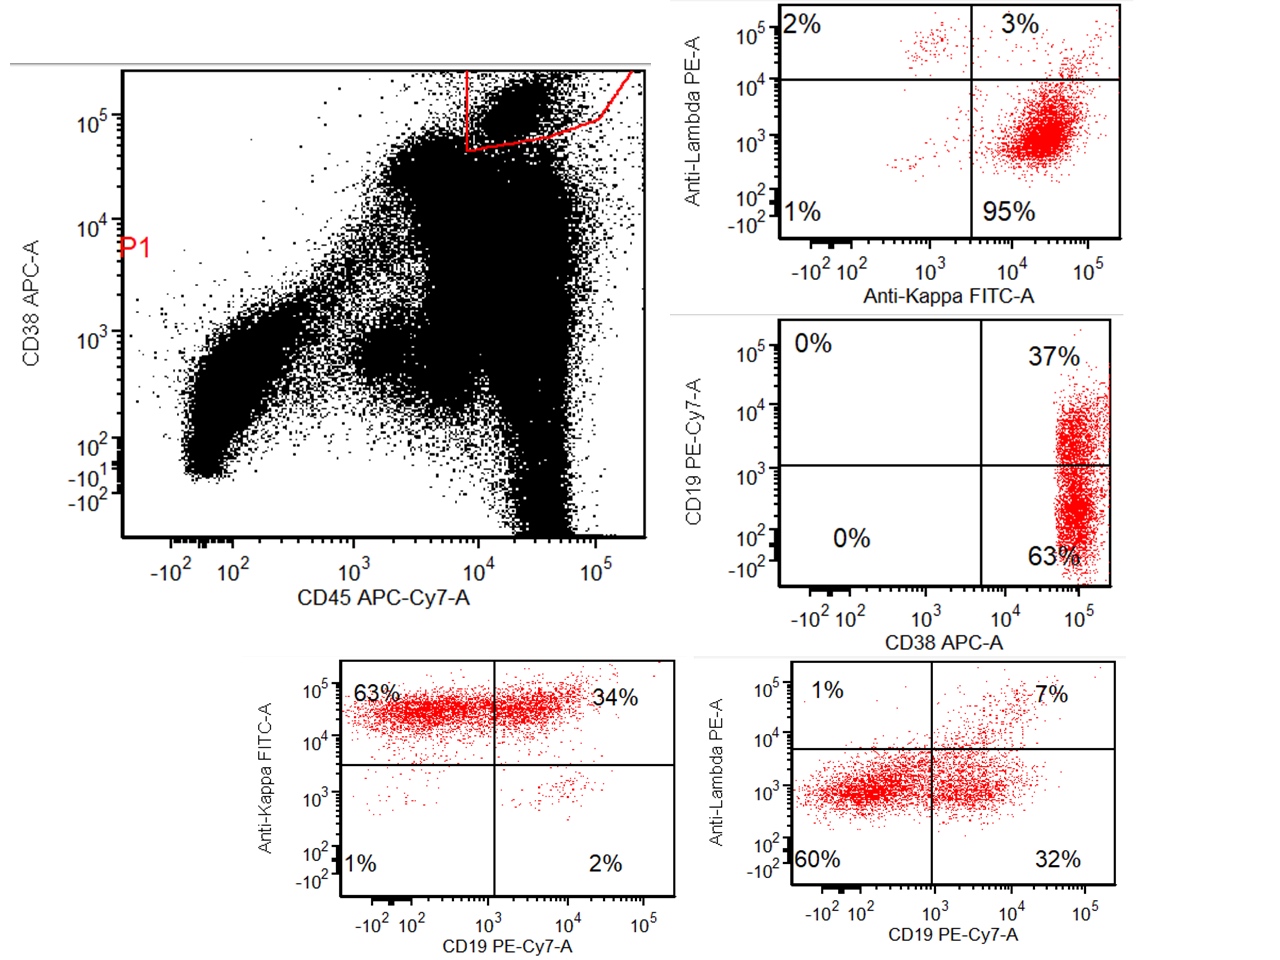

Flow cytometry description

- Monotypic cytoplasmic Ig and usually lack surface light chain

- Express CD38, CD138, often CD56+ or CD117+; may have partial CD45, usually negative for CD20, CD19 and CD10 (Cytometry B Clin Cytom 2016;90:61)

- Exception in myeloma with t(11:14) where plasma cells more often express B cell markers including CD19 and CD20

Flow cytometry images